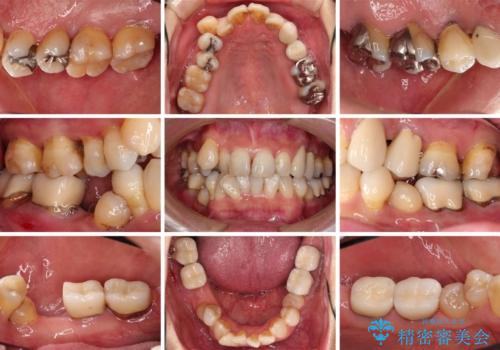

初診時に4年かかりますとお伝えし、実際に4年数ヶ月を要する治療となりました。

治療中は仮歯が頻繁に脱落したり、歯周外科によりむき出しとなった歯根が知覚過敏を起こしたりと、苦労は絶えませんでしたが、4年の治療の後にスッキリと仕上げることができました。